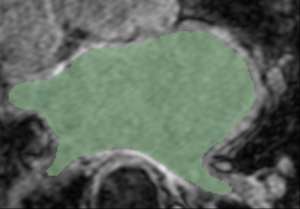

Mask and LGE Image Mask and Expert-defined Segmentation

Example 1

CARMA N24 LGE.png

CARMA N24 Endo.png

Cropped MRI image overlaid with the algorithm-defined blood pool. Expert manual segmentations (white) overlaid with the algorithm-defined blood pool (green).

Note: The last segmentation (red) was derived from an image in the atlas; the other segmentations (green) were derived from similarly-cropped images, not in the atlas.